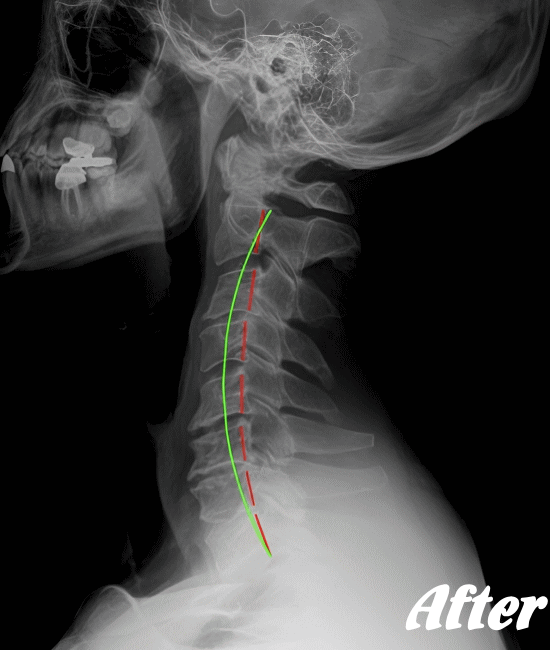

頚椎を斜め後方へ反らせると上肢に放散痛が現れたり、首の可動域、感覚異常があるかどうか…等々を確認した上で、レントゲンやCT、MRIなどによる画像検査を行います。

HALOカイロプラクティック☆平和島整体院では、骨盤から背骨全体を調整し、首(頚椎)の詰まりを一つ一つ広げ、肩甲骨の可動を柔軟にし、首周りの筋肉をゆるめることで、首の負担が解消され、痛みや痺れを改善していきます。

もちろん、再発を防ぐためには、姿勢を悪くしないように気を付けていただく必要もあります。

手術を要するヘルニアでない限り、多くの人は回復しています。